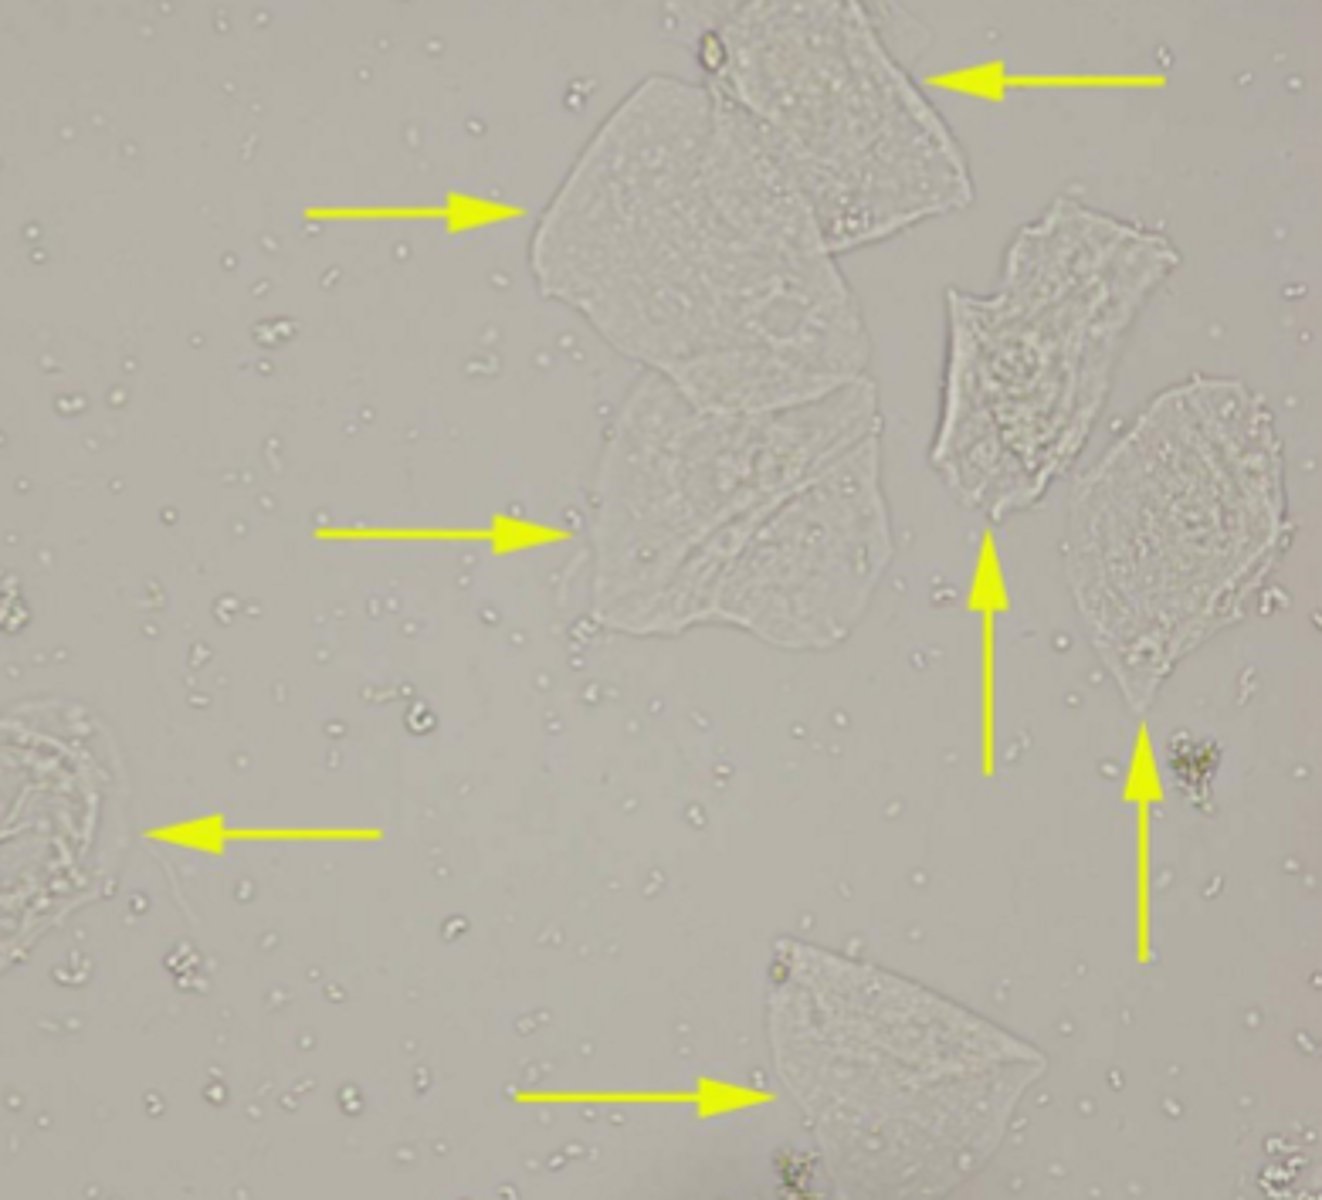

squamous epithelial cell

urine

-large, flat, irregularly shaped

-central nucleus, large amount of cytoplasm

squamous epithelial cell

urine